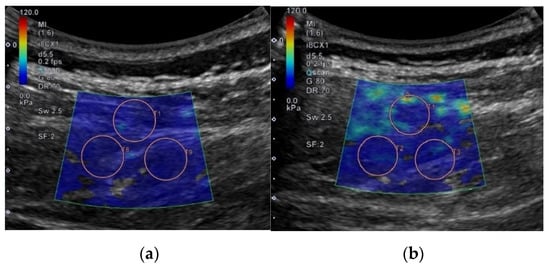

Each shear elastic modulus of the aforementioned muscles was evaluated by measuring shear-wave propagation speed in the tissue, which was generated using SWE at each measurement posture. The circular regions of interest (ROIs) were set in the color-coded boxes on the SWE mode (Figure 3). Three circular ROIs with a diameter of 10 mm were set in the color-coded box, with one located at the top–center of the box and the other two located at the inferior to the first-assigned circular ROI (Figure 3) [21,24]. Shear elastic modulus at the set ROI was automatically calculated from the ultrasound imaging device. The mean shear-elastic-modulus values of the three circular ROIs were calculated for each muscle per posture for five images. ROIs were determined by the same examiner.

Figure 3. Example for setting regions of interest to measure shear elastic modulus in different postures on flat and Wilson table. In this case, erector spinae 1 located at L3–4 is shown: (a) flat table; (b) Wilson table.